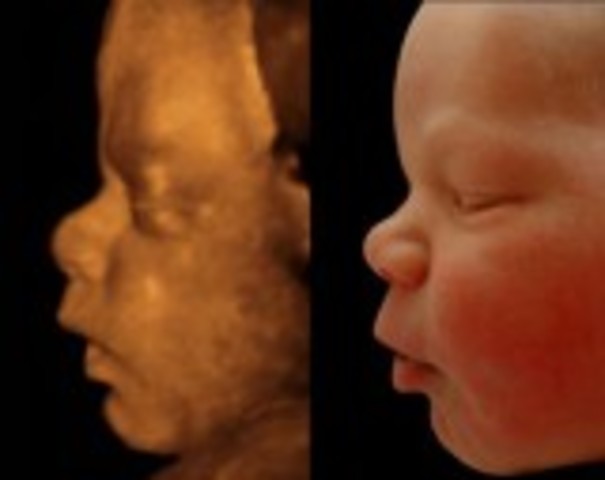

Baby starts to move. Face is beginging to take shape.

Looks are almost fully developed. Retina at the back of baby's eyes are starting to develop.